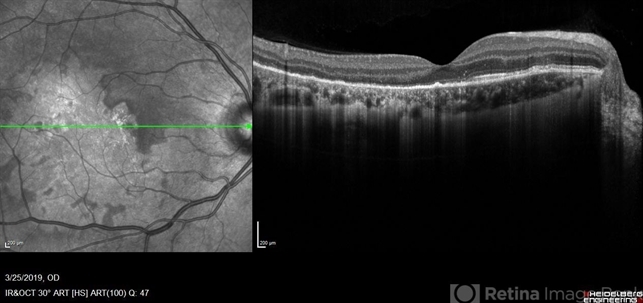

- macula serpiginous choroidopathy, macula lesion, optical coherence tomography (OCT), Heidelburg Spectralis

- Jessica Norkus

Optical coherence tomography system

Heidelberg Spectralis - Description

- Heidelberg single horizontal scan image of 20-year-old female presenting with serpiginous choroidal atrophy. Patient was unaware of vision loss OD, until accidentally covering OS and noticing the change. Acuity of 20/200 OD and 20/15 OS at time of imaging.